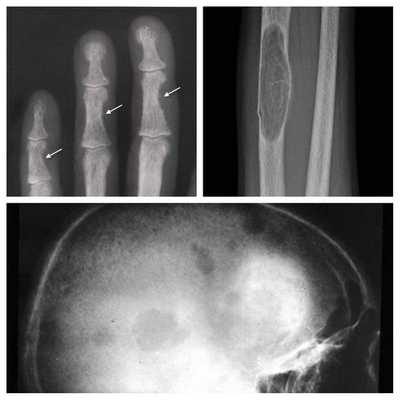

На рентгенограммах определяется остеосклероз, обызвествление реберных хрящей, по результатам денситометрии - повышенная плотность костей. МРТ выявляет отложение Ca во внутренних органах, подкожной клетчатке, ганглиях головного мозга. Для выявления скрытых форм гипопаратиреоза проводят пробы на определение повышенной судорожной готовности, пробу с гипервентиляцией.

На поздней стадии костного гиперпаратиреоза происходит размягчение, искривления, патологические переломы (при обычных движениях, в постели) костей, возникают рассеянные боли в костях рук и ног, позвоночнике. В результате остеопороза челюстей расшатываются и выпадают здоровые зубы. Из-за деформации скелета больной может стать ниже ростом. Патологические переломы малоболезненны, но заживают очень медленно, часто с деформациями конечностей и образованием ложных суставов. На руках и ногах обнаруживаются периартикулярные кальцинаты. На шее в области паращитовидных желез можно пальпировать большую аденому.

Рентгенография позволяет обнаружить остеопороз, кистозные изменения костей, патологические переломы. Для оценки плотности костной ткани проводится денситометрия. При помощи рентгенологического исследования с контрастным веществом диагностируют возникающие при гиперпаратиреозе пептические язвы в желудочно-кишечном тракте. КТ почек и мочевыводящих путей выявляет камни. Рентгенотомография загрудинного пространства с пищеводным контрастированием бариевой взвесью позволяет выявить паратиреоаденому и ее местоположнение. Магнитно–резонансная томография по информативности превосходит КТ и УЗИ, визуализирует любую локализацию околощитовидных желез.

Длительное течение заболевания сказывается на формировании костей. Так, н а поздних стадиях вовремя не диагностированного гиперпаратиреоза наблюдаются:

- разрушение дистальных или концевых фаланг конечностей;

- сужение дистального отдела ключиц;

- очаги разрушения костей черепа;

- бурые опухоли длинных костей.